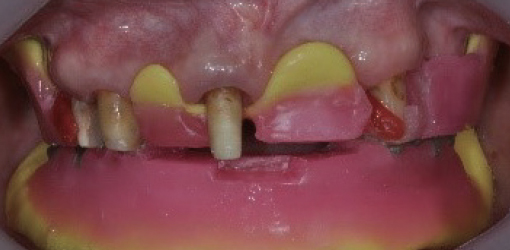

2. Mount the prepared occlusal wax rim intraorally and take the posterior bite conventionally using Aluwax

3. Apply PVS bite registration material on residual teeth or occlusal wax rim

2. Mount the prepared occlusal wax rim intraorally and take the posterior bite conventionally using Aluwax

3. Apply PVS bite registration material on residual teeth or occlusal wax rim